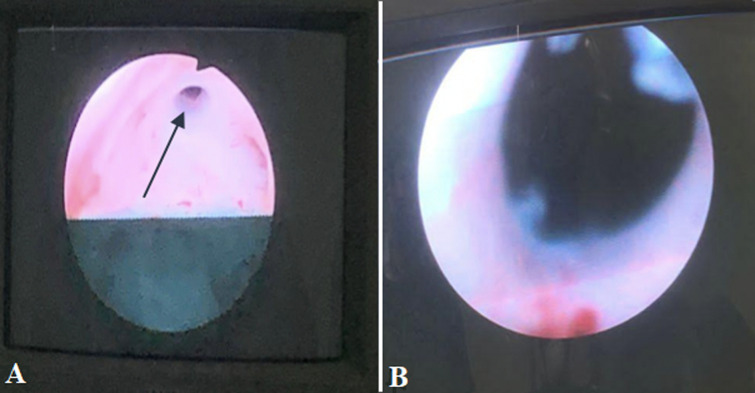

结石的形成可能是由于膀胱憩室的尿液淤积所致。然而,结石通常体积较小,可以自行排出。然而,膀胱憩室内的巨大结石被认为是罕见的实体。我们报告一位69岁男性,有两年的下尿路症状史,并伴有尿路感染复发。腹部计算机断层扫描显示存在巨大膀胱憩室和大膀胱结石。患者接受经尿道膀胱颈部切口,随后行憩室切除术并取出结石。憩室尺寸为6x4x3.8厘米,憩室结石尺寸为4x3x3厘米。幸运的是,病人手术后恢复得很好。综上所述,大膀胱憩室内的巨大结石是罕见的,在有下尿路症状的患者中应予以考虑。早期诊断和最佳处理是预防长期并发症的原则。

The stone formation could occur due to urine stasis in the bladder diverticulum. However, the stones are usually smaller in size and can pass spontaneously. However, a giant stone inside vesical diverticulum is considered a rare entity. We report a 69-year-old male, with a two-year history of lower urinary tract symptoms along with a recurrence of urinary tract infection. An abdominal computed tomography scan revealed the presence of a giant bladder diverticulum and a large bladder stone. The patient underwent a transurethral bladder neck incision followed by diverticulectomy with stone extraction. The diverticulum size measures 6x4x3.8 cm and diverticulum stone size of 4x3x3 cm. Fortunately, the patient recovered well after the operation. In conclusion, giant stones inside large vesical diverticulum are a rare occurrence and should be considered in patients with lower urinary tract symptoms. Early diagnosis and optimal management of the obstruction are the principles to prevent long-term complications.